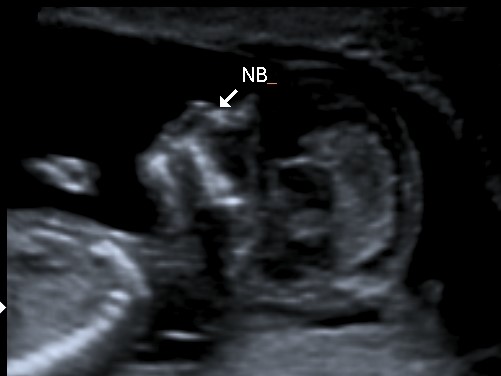

Hi Ladies! I'm new to this site and swayed pink hoping for a girl this time after 2 beautiful boys. Looking at the skull of this lo it is a lot more rounded and looks different to both my boys so i'm leaning towards this may be my girl.

No good nub shots though. This is bubs skull, potty shot (though baby was 12&1 at my scan but measuring ahead at 13wks, so I think its way too early) and a side profile. Would love some educated guesses.